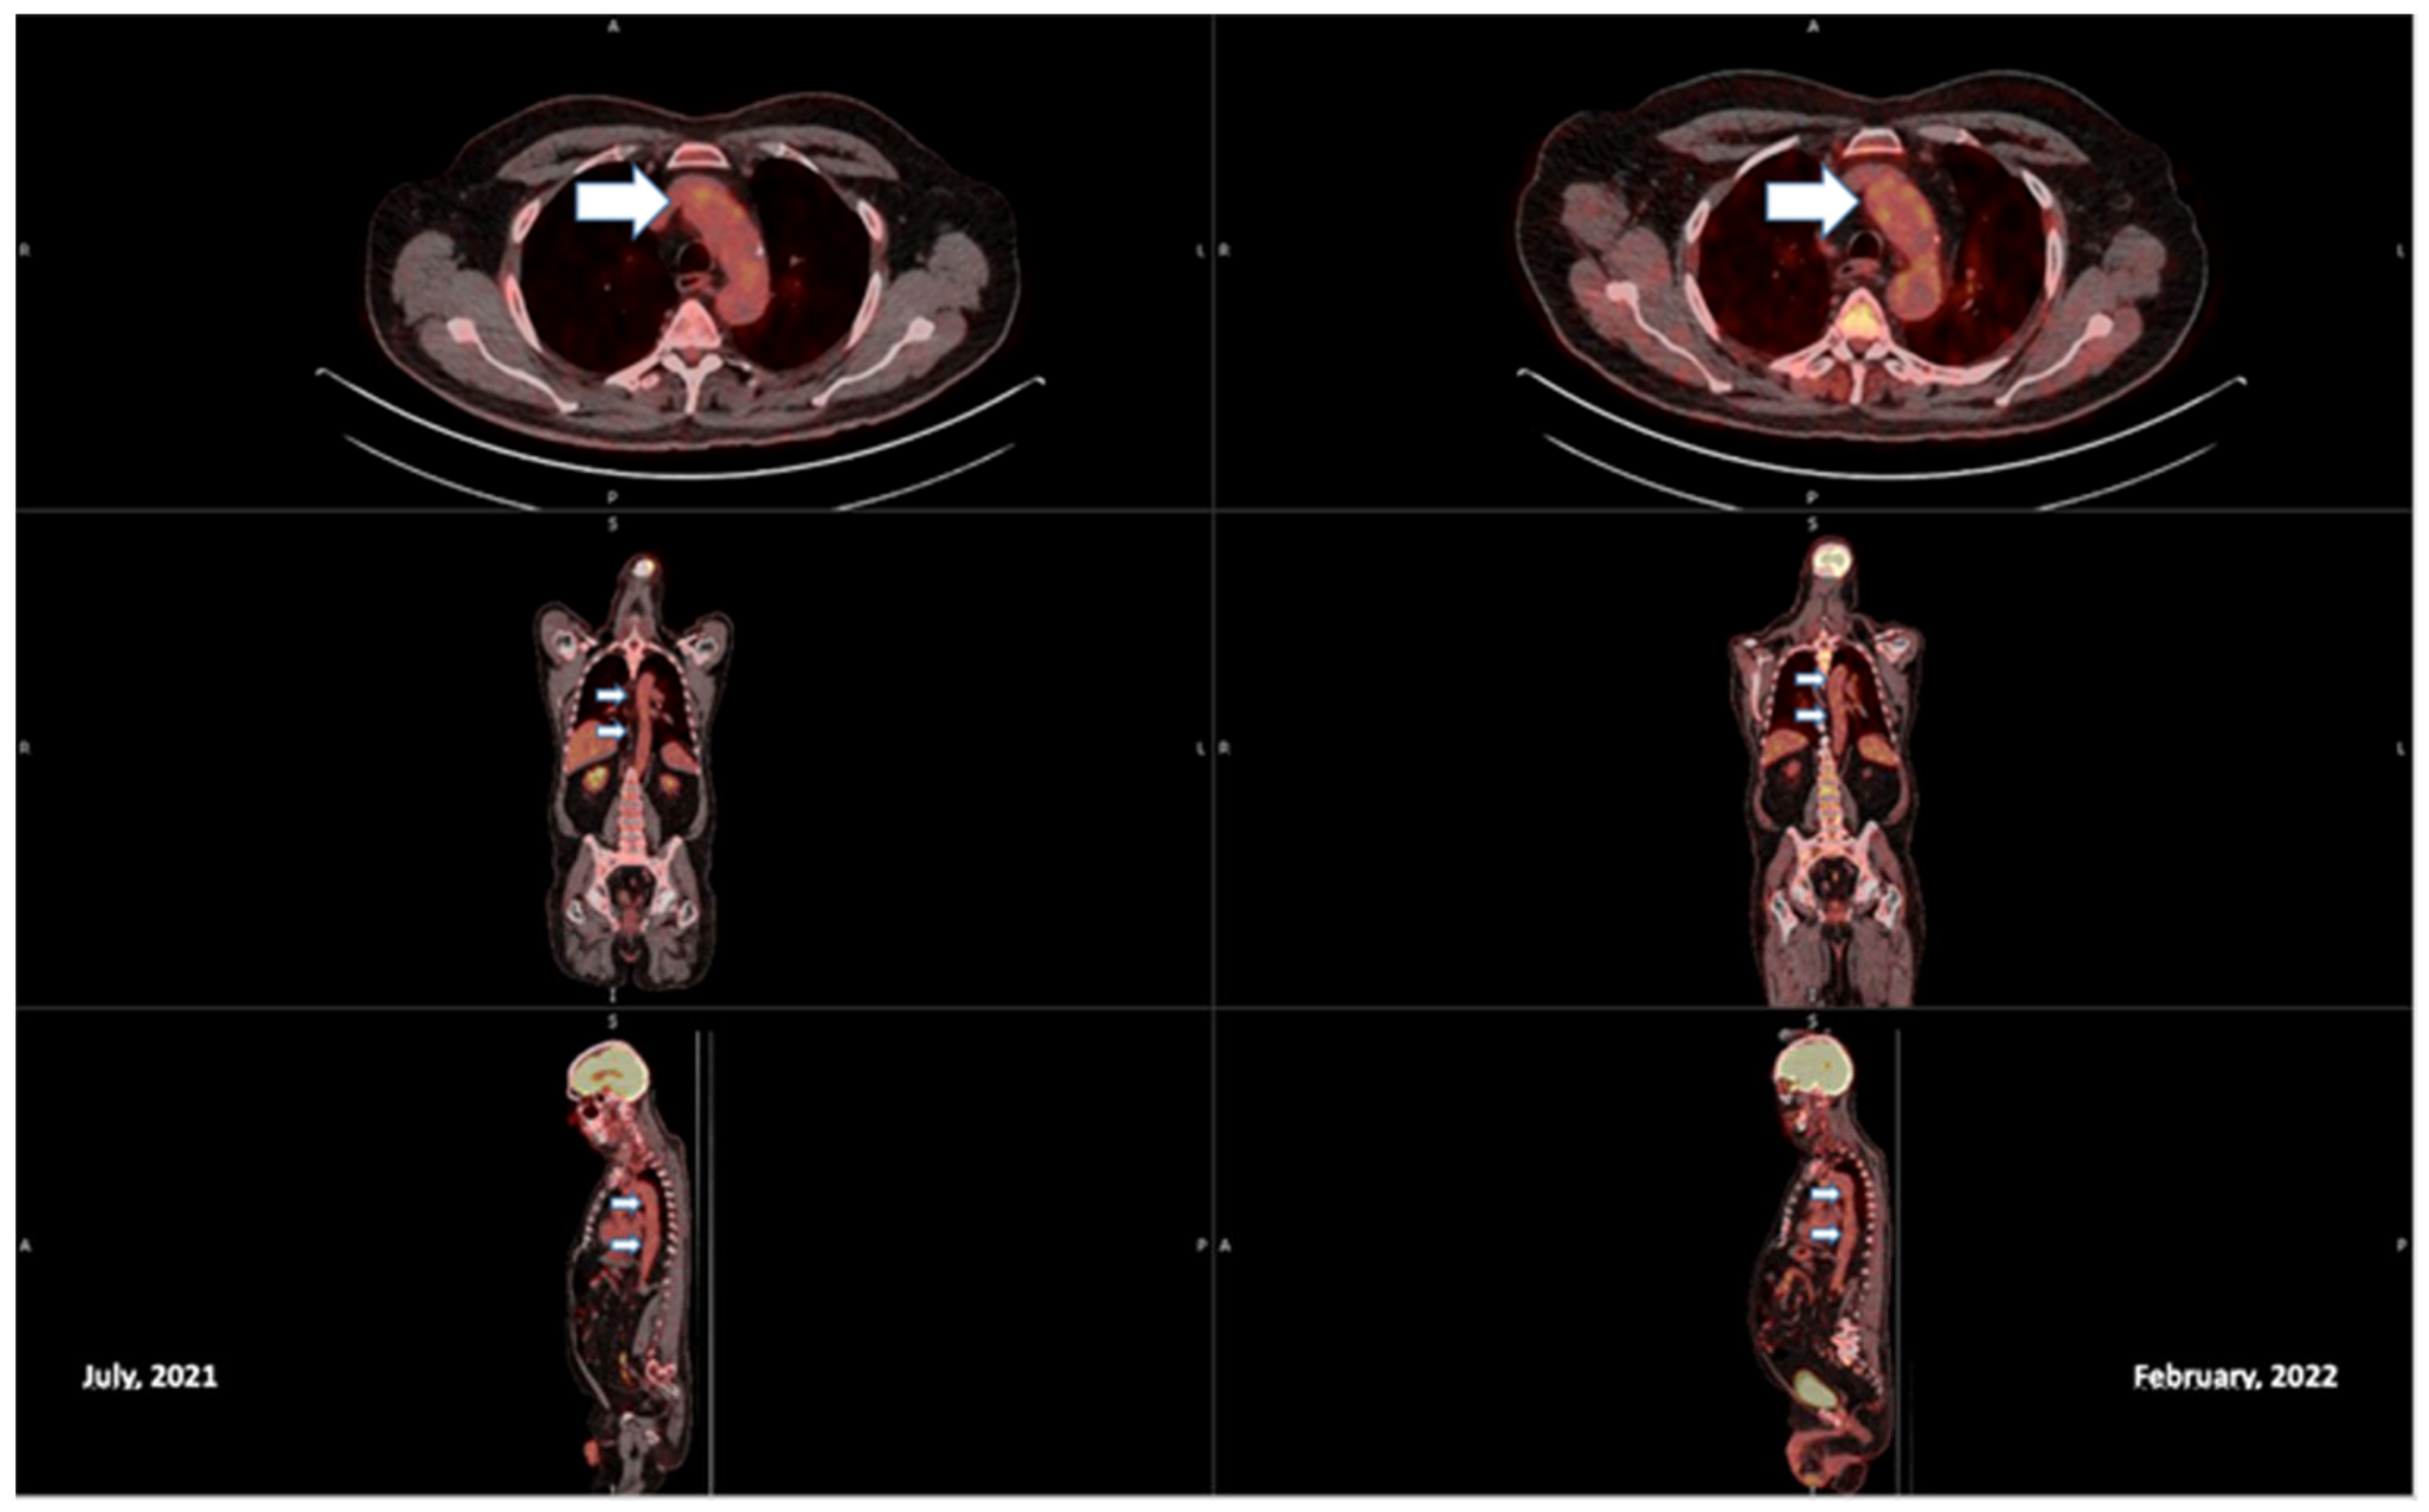

2. Case Report